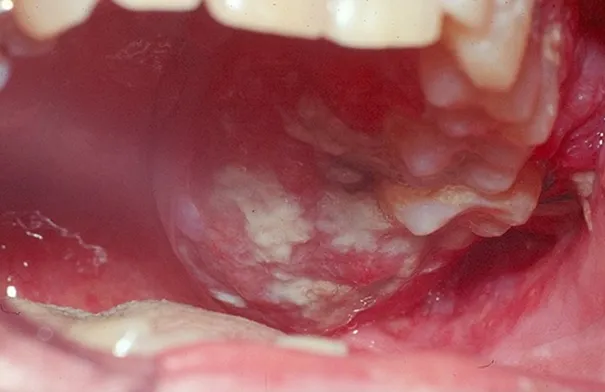

طب و صحة

• لماذا لا يجب غسل العدسات اللاصقة بالماء.. طبيبة تقدم أهم النصائح

• ضغط نهاية السنة.. كيف تهدّئ توتر العمل في موسم الأعياد؟

• 5 تمارين ذهنية لتنشيط الدماغ بعد سن الأربعين

• مكملات الزنك: فوائدها لا تمنع "الجرعة الزائدة" من المخاطر

• لماذا نحمرّ خجلاً؟ فوائد اجتماعية لاحمرار الخدود

• تنميل الوجه المفاجئ.. إشارة لا تُهمل

• ألعاب الفيديو وسيلة فعّالة لتخفيف التوتر لدى الشباب.. اليكم ما كشفته الدراسات

• كيف يحمي التشخيص المبكر من تصلب الشرايين؟

• طبيب يحذر من النوم المتأخر .. التوقيت أهم من عدد الساعات

• أطباء يحسمون حقيقة أخطر خرافة حول النوم بجوار الهاتف

• اكتشاف نوع نادر من السكري يصيب حديثي الولادة حول العالم

• هل الوجبات الخفيفة بريئة فعلًا أم سبب خفي لزيادة الوزن؟

• من خلال هذه الاطعمة.. كيف تقوي مناعتك في البرد؟

• من الطعام والماء والهواء.. ميكروبلاستيك يستقر في الأعضاء ويؤذي الأوعية

• أطعمة صحية تساعد على التعافي من "الإنفلونزا الخارقة".. ما هي؟

• هل يؤثر ترتيب تناول الطعام على صحتك؟ إليك أفضل ما يجب البدء به

• إعطاء الطفل هاتفاً قبل هذا العمر مضر جداً .. دراسة تؤكد

• اكتشاف نوع نادر من السكري يصيب حديثي الولادة مرتبط بطفرة جينية جديدة

• فيتامين C من الطعام.. مفتاح صحة البشرة ونضارتها من الداخل

• كيف يؤثر قصور الغدة الدرقية على ملامح الوجه؟